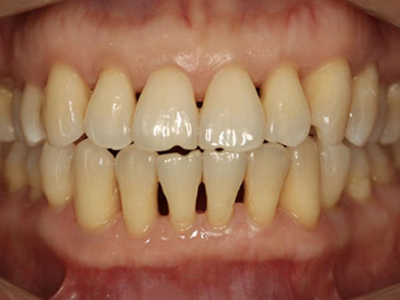

牙龈退缩牙龈轻度萎缩图

牙龈退缩患者的上排牙和下排牙多颗牙齿的牙龈发生回缩,从而造成牙根轻微暴露,患者会出现牙根面敏感、口臭等症状,需要牙周治疗或脱敏治疗。